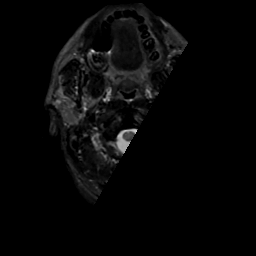

MR Study #15, June 9, 1991 -- Slice #0

[Home][Help][Clinical][Tour 1][Tour 2] Slice 0